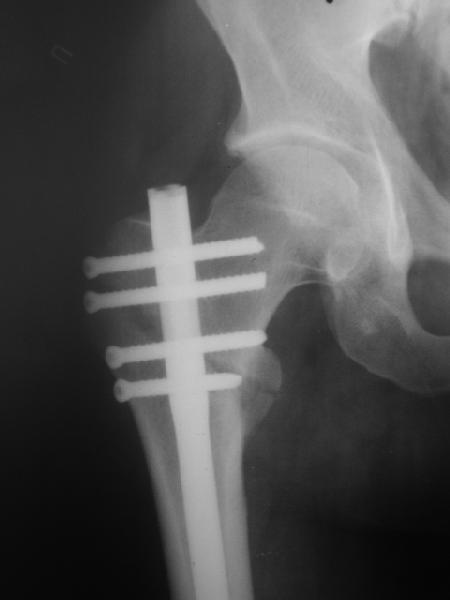

При межвертельных переломах с цефаломедуллярными гвоздями бывает, что проксимальый винт проходит или черед периферический отломок, или прямо над ним. И если остался диастаз, то этот винт при осевой нагрузке не дает сблизиться отломкам. Пример такого остеосинтеза в застарелом случае в приложении.

В качестве предупреждающей меры можно долотом разрушить латеральную стенку дистального отломка под винтом.

В частности, на проксимальном конце сделано еще одно дополнительное статическое отверстие. Можно ввести в проксимальном отделе 4 винта, из них 3 статические (2 в круглые отверстия и 1 по нижнему краю овального). Картинки в приложении. На дистальном конце стержня тоже кое-что улучшено. Спрашивайте в аптеках, как говорится. Выпускается предприятием "ЦИТО" (Москва), то есть это малобюджетное решение.

Конечно, мы не синтезируем остеопорозые вертельные переломы согласно прилагаемому примеру, винты 6 мм вырежутся. Но у более молодых при хорошем качестве кости такие или подобные гвозди с поперечным расположением винтов вполне применимы для меж- и подвертельных переломов.

Это было года 2,5 назад, мы тогда еще уточняли возможности шинирования с угловой стабильностью гвоздем с поперечным расположением винтов при переломах проксимального отдела бедра. Пациенту не пришлось приобретать намного более дорогой рекон или проксимальный гвоздь. В приложении еще несколько примеров применения того гвоздя при высоких переломах бедра, в том числе с более латеральной точкой входа. Гвоздь изгибаем для этого.